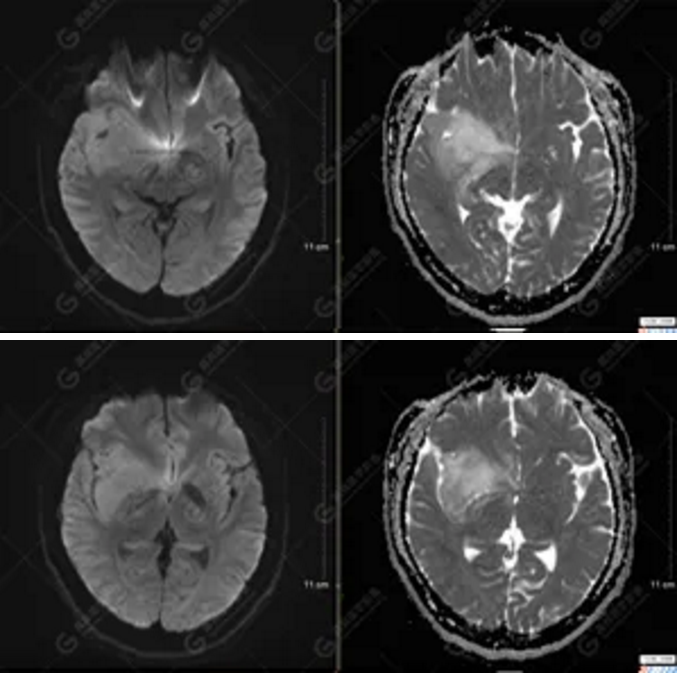

以上為DTI成像,圖1為皮質(zhì)脊髓束,圖2為胼胝體束,圖3為扣帶回束,圖4為額枕束。DTI成像示右側(cè)額枕束前部明顯受壓、部分未見顯示;胼胝體束、雙側(cè)扣帶束、皮質(zhì)脊髓束及左側(cè)額枕束形態(tài)可,纖維束未見明顯破壞,未見明顯稀疏減少。

1.右側(cè)額顳島葉、右側(cè)海馬及右側(cè)基底節(jié)區(qū)占位病變,考慮為彌漫性星形細(xì)胞瘤可能性大,累及右側(cè)大腦中動脈、右側(cè)下丘腦及視交叉;

2.DTI成像示右側(cè)額枕束前部明顯受壓、部分未見顯示。